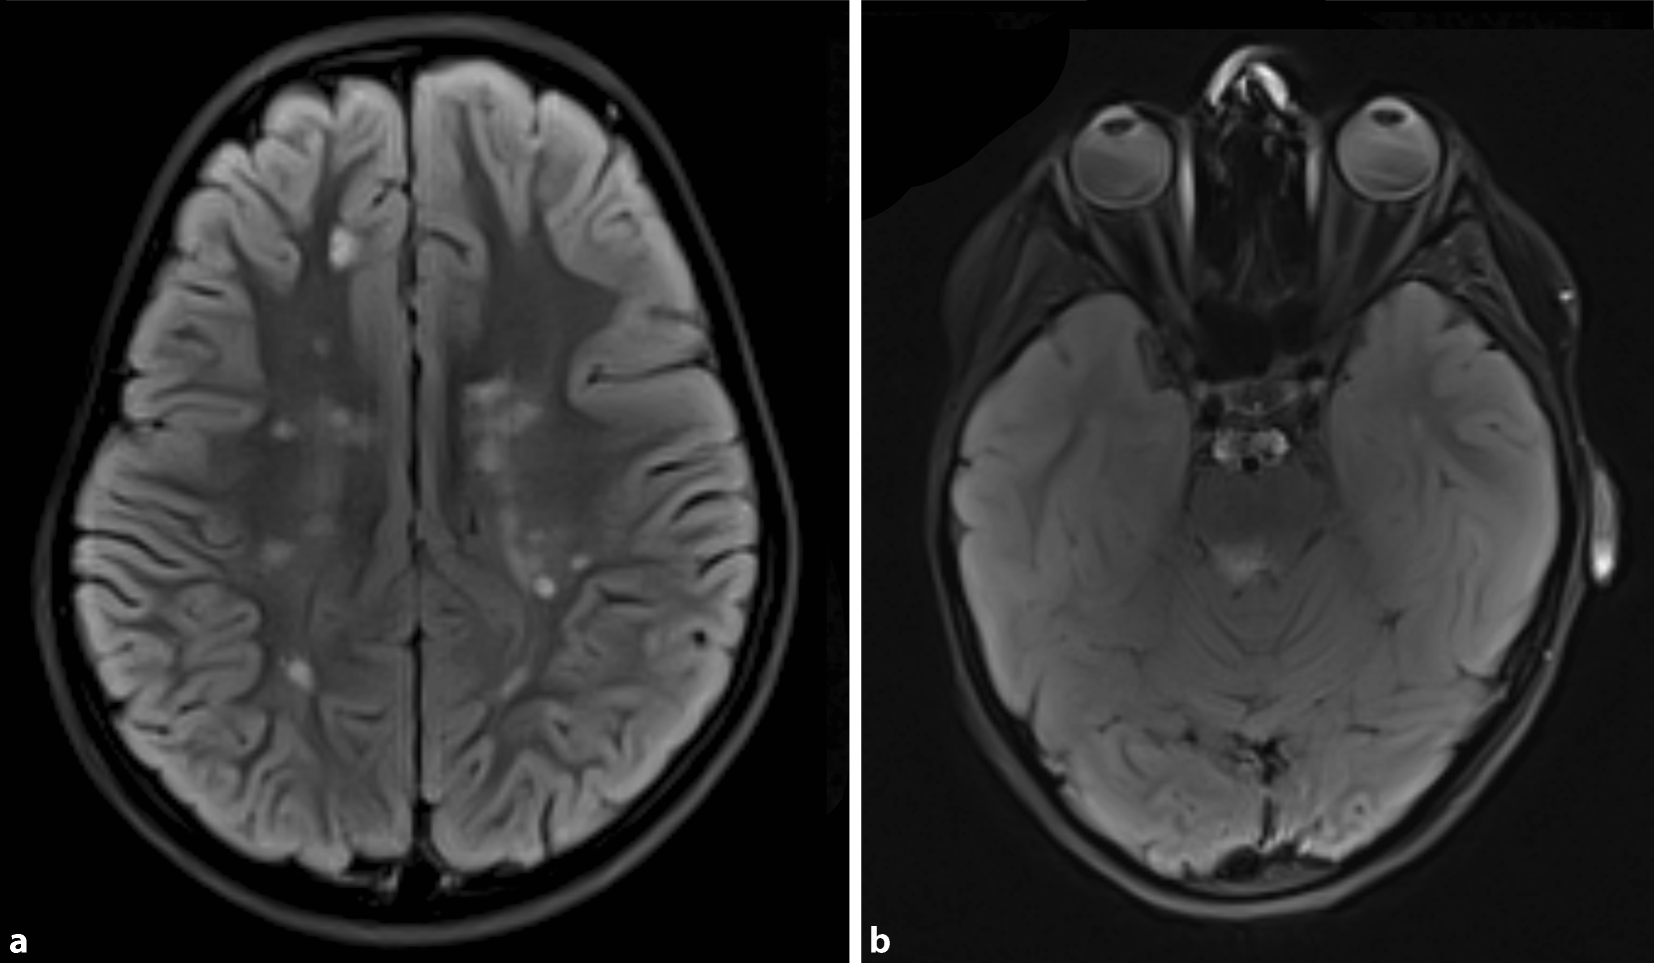

Darüber hinaus wurde die Empfehlung zu einer krankheitsmodifizierenden Therapie mit Fingolimod unter der Annahme einer wahrscheinlich hochaktiven, schubförmigen bzw. rasch fortschreitenden Verlaufsform einer MS ausgesprochen. Dieser konnten sich die Eltern genauso wenig anschließen wie einer ebenfalls diskutierten Interferontherapie. Stattdessen entschieden sie sich für eine alternativmedizinische Behandlung. Es konnte lediglich eine MRT-Verlaufskontrolle nach 3 Monaten vereinbart werden. In dieser Untersuchung wurde eine neue T2-hyperintense Marklagerläsion auf Höhe des Trigonums des rechten Seitenventrikels festgestellt (Abb. 3). Aufgrund dessen wurde erneut der Beginn einer immunmodulierenden Therapie empfohlen. Zur Einholung einer Zweitmeinung wurde eine ambulante Vorstellung in einem Kompetenzzentrum für MS im Kindesalter nahegelegt.

Abb. 3

T2-gewichtete cMRT-Aufnahme im Verlauf nach 3 Monaten mit neu nachgewiesenen Marklagerläsionen auf Höhe des Trigonums des rechten Seitenventrikels